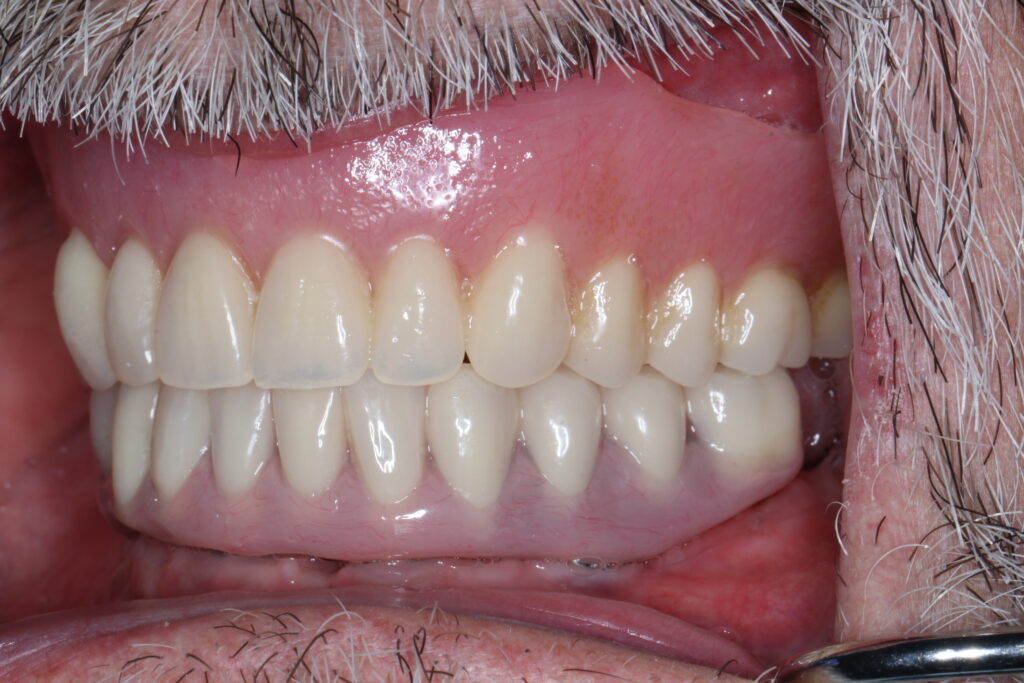

A selection of full arch fixed implant bridge patients after 5 years of wear

Oral Surgeons – Dr Han Choi, Dr Sam Goldsmith, Dr Rajiv Rajpal NSOMS

Prosthodontist – Dr Alan Payne NSOMS/Northland Prosthodontics

Dental technicians – Hosaka Takashi, DT Denture Design, Auckland, CJ Park, Project Dentistry, Auckland and Osteon Medical, Melbourne, Australia.